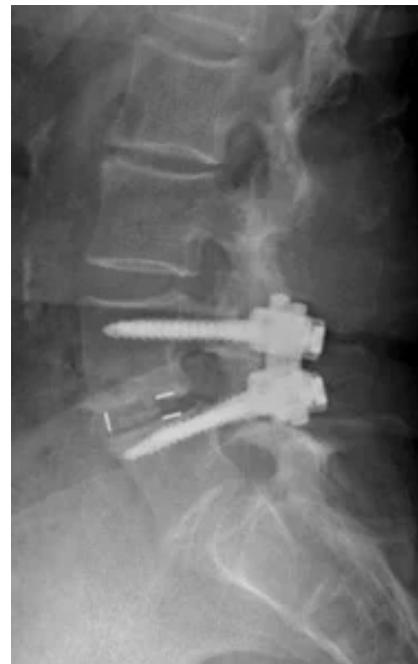

Degenerative Spondylolisthesis

- Definition: Common degenerative condition characterized by subluxation of one vertebral body anterior to the adjacent inferior vertebral body with intact pars

- Demographics: Most common in females over 40 years of age, at the L4-5 level

- Diagnosis: Lateral radiographs; flexion and extension lateral lumbar radiographs can identify degree of instability

- MRI: Helpful for central or foraminal stenosis

Treatment:

- Nonoperative: Trial with NSAIDs and physical therapy

- Surgical: Indicated for progressive disabling pain that has failed nonoperative management, and/or progressive neurological deficits